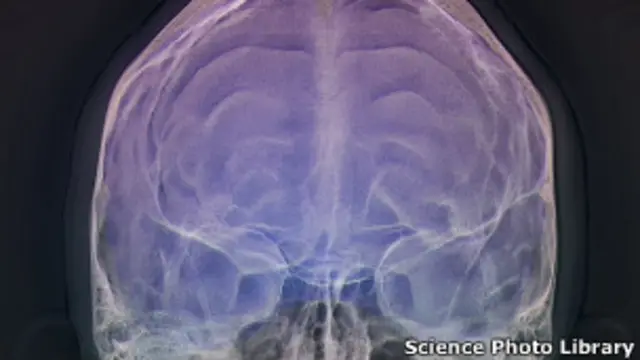

Fuente de la imagen, Science Photo Library